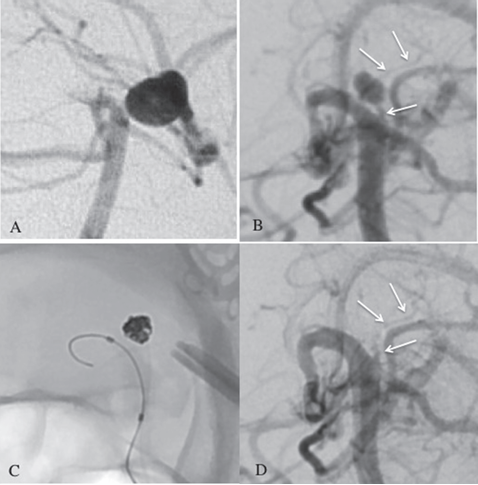

在进行急性脑积水双侧脑室外引流后,对符女士进行数字减影血管造影(DSA)。

右椎动脉血管造影(VAG)显示一个小的动脉瘤(4 × 4 mm),起源于闭塞的左侧 P1 上部的穿通动脉,但左侧 P1 的远端部分仍然闭塞。

检查没有发现其他动脉瘤或异常血管,因此诊断为新发 pTPA 破裂的动脉瘤,并计划对此动脉瘤进行弹簧圈栓塞。但手术难度和风险很高:

- (A)既往 DSA 显示左侧 PCA 未通,无 BA 尖端动脉瘤。

- (B)右侧椎体血管造影显示丘脑后穿通动脉(pTPA)动脉瘤。pTPA(白色箭头)起源于闭塞的左侧 P1 孔。

- (C&D)采用六个弹簧圈实现了完全闭塞。弹簧圈栓塞后检测到丘脑后方穿通动脉 (白色箭头)。

川岛教授团队采用血管内弹簧圈栓塞术,在全身麻醉后进行系统肝素化。一根引导管位于右椎动脉中,一根微球导管插入到右侧 PCA 中。

通过右椎动脉入路,将微导管精准送至动脉瘤颈部,释放6枚1.5×3cm弹簧圈完全填塞瘤腔。

术后CT未见脑梗死,MRS评分4分(可独立行走但需辅助)。